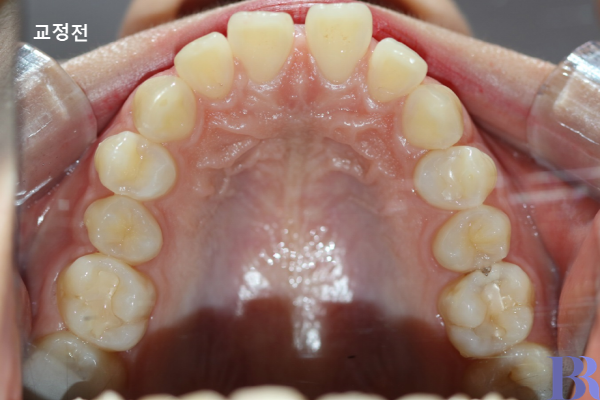

보통 편측발치 케이스에서는 상악 제1소구치를 발치하게 됩니다.

위 환자분은 상악 제1소구치

두 곳에 발치를 진행했습니다.

발치교정 케이스 : 윗니 악궁 전후 모습,

상악 제1소구치(첫번째 작은 어금니)가

발치된 것이 확인되고 있음.

위 사진은 교정 전후 윗니입니다.

첫번째 작은 어금니를 발치하여

교정한 것을 알 수 있습니다